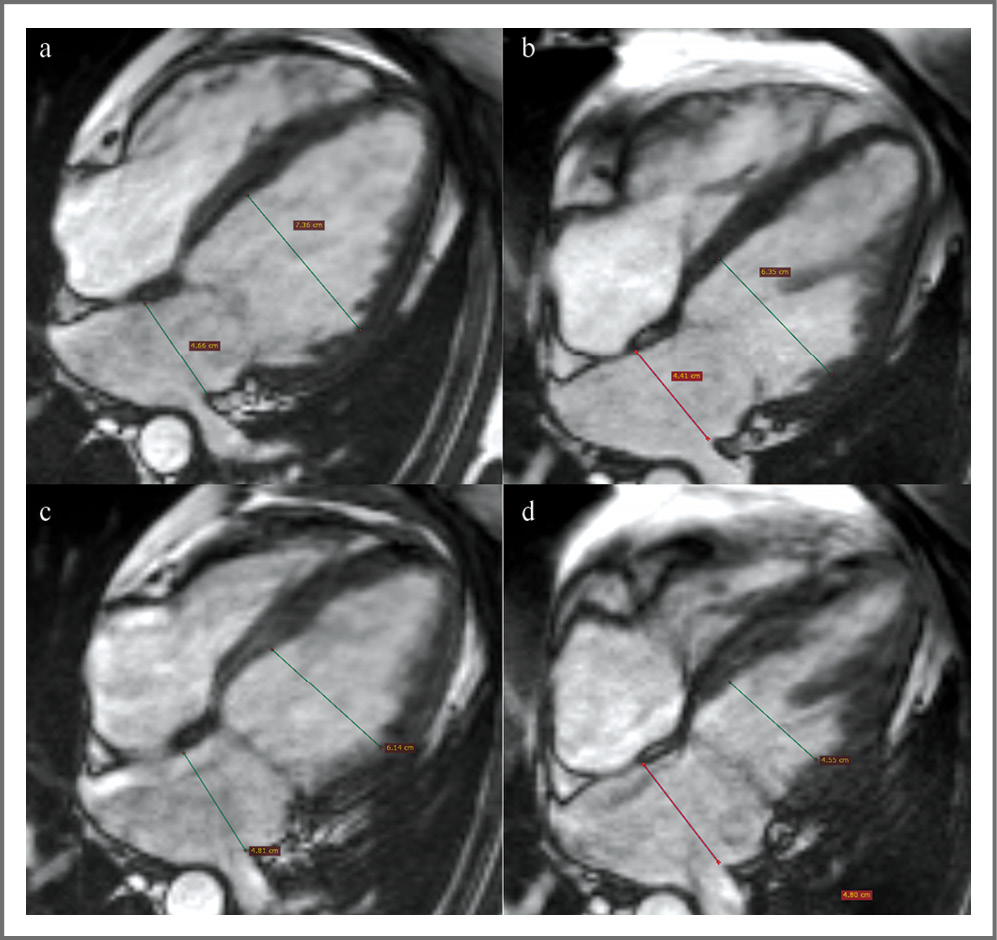

При оценке по 5-балльной шкале оценивалось наличие фиброза по данным МРТ сердца с контрастированием до и после терапии дапаглифлозином, по данным которой не отмечается прогрессирование фиброза (рис. 2).

Рис. 2. МРТ сердца с отсроченным контрастированием после введения гадолиний-содержащего препарата (импульсная последовательность PSIR). Сечение по короткой оси ЛЖ (a, c) и четырехкамерная проекция (b, d). Стрелками обозначен постинфарктный рубец. Изображения до лечения (a, b) и после лечения (c, d).

МРТ показало отсутствие динамики размеров и конфигурации зоны фиброза миокарда при сравнении снимков до и после лечения.

Fig. 2. Cardiac MRI with delayed contrast after introduction of gadolinium containing drug (pulse sequence PSIR). A section on the short axis of the left ventricle (a, c) and a four-chamber projection (b, d). The arrows mark the postinfarction cicatricial changes. Images before treatment (a, b) and after treatment (c, d).

При расчете показателя количественной оценки фиброза миокарда через 6 мес наблюдалось меньшее по сравнению с исходным значение объема фиброза миокарда. Изменения не являлись статистически значимыми (табл. 5).